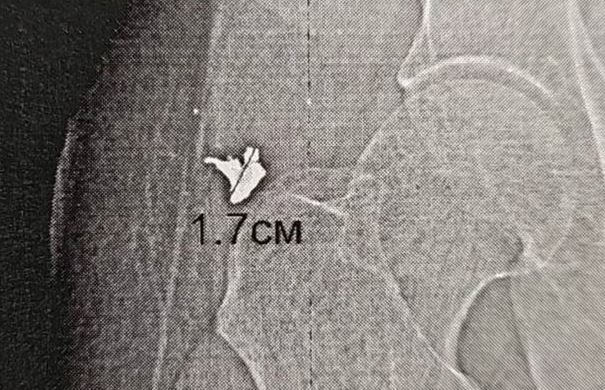

Местный житель получил травмы во время атаки беспилотников весной прошлого года. Тогда врачи сделали все возможное, чтобы поставить пострадавшего на ноги, но глубоко засевший в бедре осколок удалить не получилось.

Позже у пациента началось воспаление, образовался абсцесс. Операцию проводил Рустам Ефремов из Ноябрьской больницы, отправившийся в подшефный регион в августе. Под контролем рентгена он извлек осколок и установил дренаж.